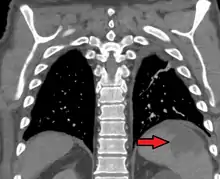

Splenic infarct seen on CT

An abdominal CT scan is the most commonly used modality to confirm the diagnosis,[3] although abdominal ultrasound can also contribute.[5][6][7]